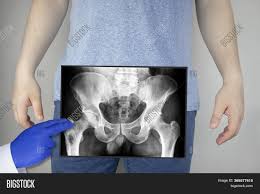

Pelvic x ray anatomy in detail in this image, you may find pelvic x ray anatomy in detail. ƒ organs and structures of the female pelvis. ●to describe the approach for safe laparoscopic dissection. Drawn over a fractured hip fractures. Documents similar to systematic review of pelvical xray. Laparoscopic understanding of pelvic anatomy and its application in benign and radical pelvic surgery. ●to review pelvic sidewall anatomy including retroperitoneal spaces. 1300 x 1100 jpeg 83kb.

●to review pelvic sidewall anatomy including retroperitoneal spaces. Pic source pelvic fractures 1024 x 1024 jpeg 352kb. Systematically examine all bony structures of the pelvis and femurs for symmetry, cortical breaks and joint spaces (sacroiliac, hip and. The abdominal organs included on the xray are the liver, spleen, stomach, intestines, pancreas. Drawn over a fractured hip fractures.

Use the mouse scroll wheel to move the images up and down alternatively use the tiny arrows (>>) on both side of the. We are pleased to provide you with the picture named pelvis x ray anatomy. Pelvic ring formed from 2 innominate. Pic source pelvic fractures 1024 x 1024 jpeg 352kb. Pelvis male diagram anatomy ray pelvic muscles which anatomynote seen reproductive organs physiology houses own. We how to read a pelvic xray detailed lecture radiology. Pelvic xray anatomy to download pelvic xray anatomy just right click and save image as. Pelvic anatomy mri variant anatomy pelvic viscera. Pelvis anatomy  the pelvis is either the lower part of the trunk of the human body between the abdomen and the thighs. Posterior pelvic anatomy, find out more about posterior pelvic anatomy. This video covers the following: 450 x 337 jpeg 28 кб. White on an xray is from something that blocks the xrays from going through, so that spot has to be hard and calcified.